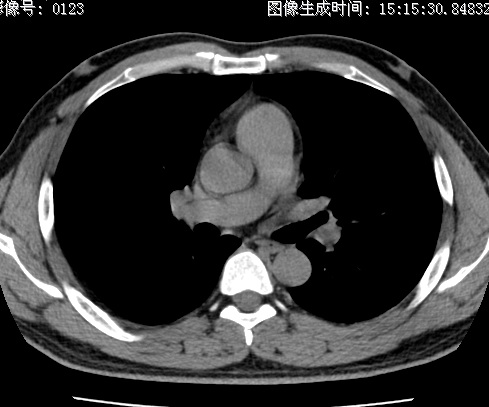

以下是引用zhao_bin2008在2010-1-4 20:15:00的发言:[br]先天性肺囊肿或小的肺隔离症?

以下是引用卜一在2010-1-4 22:09:00的发言:[br]先天性肺囊肿或小的肺隔离症?支持!

以下是引用zsl6918在2010-1-5 5:23:00的发言:[br]良性改变!肺囊肿,先天性支气管闭锁,血管畸形等均有可能。

以下是引用影像之路在2010-1-6 11:10:00的发言:[br]腺癌,最终的病检有些出乎意料之外,术前同志们大多考虑为肺囊肿或小的肺隔离征 [br]回过头来看 小结节呈分叶状,其内侧有一条较粗的静脉供血或许能成为支持诊断腺癌的理由